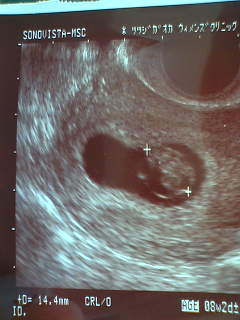

おおお!人間の形になっている!!

毎日気持ち悪くてジャンクフード三昧、お昼寝三昧の

ゆる~いひきこもり生活の私の我が子"もこみち"は、

きちんと一日一ミリ成長し、14mmになっていた。

そして、透け透けの皮膚の下をぐるぐる流れる液体と

ちっちゃいながらも、ぴこぴこ動く心臓がモニターで確認できる。

ちょっと感動♪